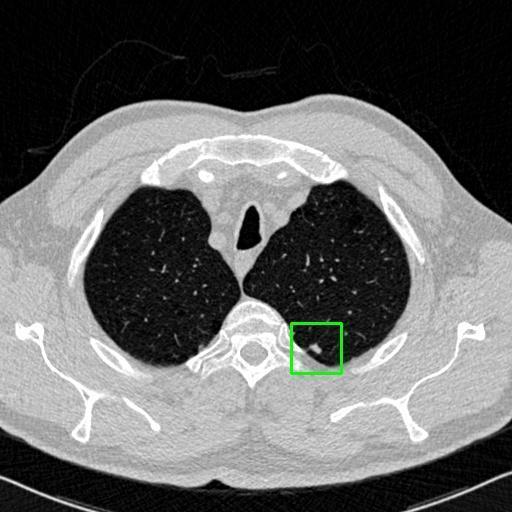

We developed an AI-based system using deep learning models for analyzing lung CT scans to detect and classify pulmonary nodules. We chose the YOLOv11 architecture for its enhanced object detection capability and adapted it specifically for medical imaging, incorporating pixel-level precision and severity classification.

Classification into three severity levels with colored bounding boxes.

Successfully built and deployed an AI model (YOLOv11) capable of detecting lung nodules in CT scans with high accuracy and real-time performance.

Designed a severity classification system that categorizes nodules into null, moderate, and severe using colored bounding boxes, assisting in rapid clinical decision-making.